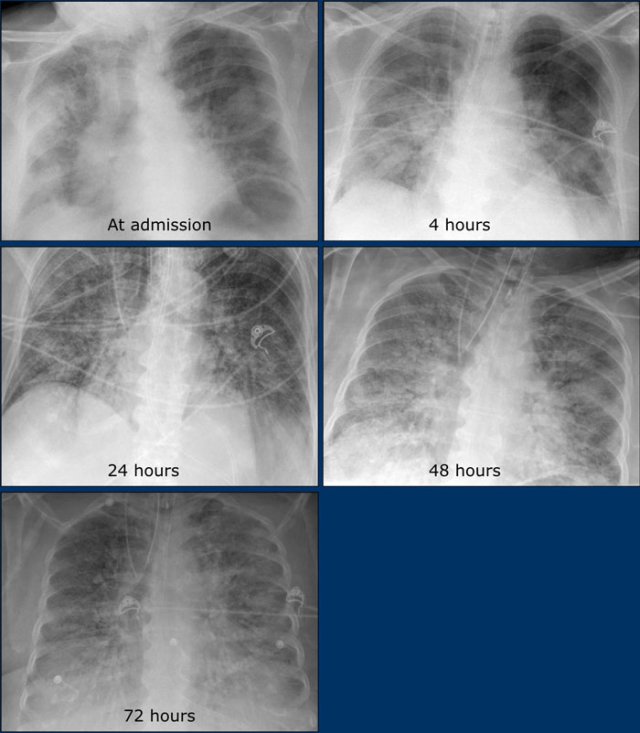

A series of chest films of a 72-year-old woman admitted with acute respiratory failure, fever (38ºC) and dyspnoea.

She was tachypneic (30bpm), with lymphopenia and low oxygen saturation (SpO2 85%).

Patient presented to the emergency department two days earlier with fever (up to 38.6ºC), dry cough, odynophagia and general malaise.

She was discharged from hospital because she did not present alarm criteria at that time.

The patient required mechanical ventilation and was admitted to intensive care.

During her stay in ICU, poor evolution to respiratory distress syndrome and to multi-organic failure.

The patient died 24 hours later.

Imaging findings:

• At admission: Ill-defined bilateral alveolar consolidation with peripheral distribution.

• 4 hours later: Radiological worsening, with affectation of lower lobes. Endotracheal tube and central venous line were required.

• 24 hours: Bilateral alveolar consolidation.

• 48 hours: Radiological worsening. Bilateral alveolar consolidation with panlobar affectation.

• 72 hours: Bilateral alveolar consolidation with panlobar affectation, with typical radiological findings of ARDS. 24 hours later the patient passed away.